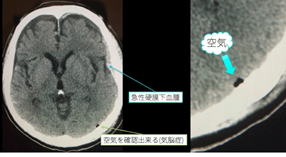

体内に閉鎖腔がある患者.

例:耳管閉塞、気胸、腸閉塞、気脳症、等。